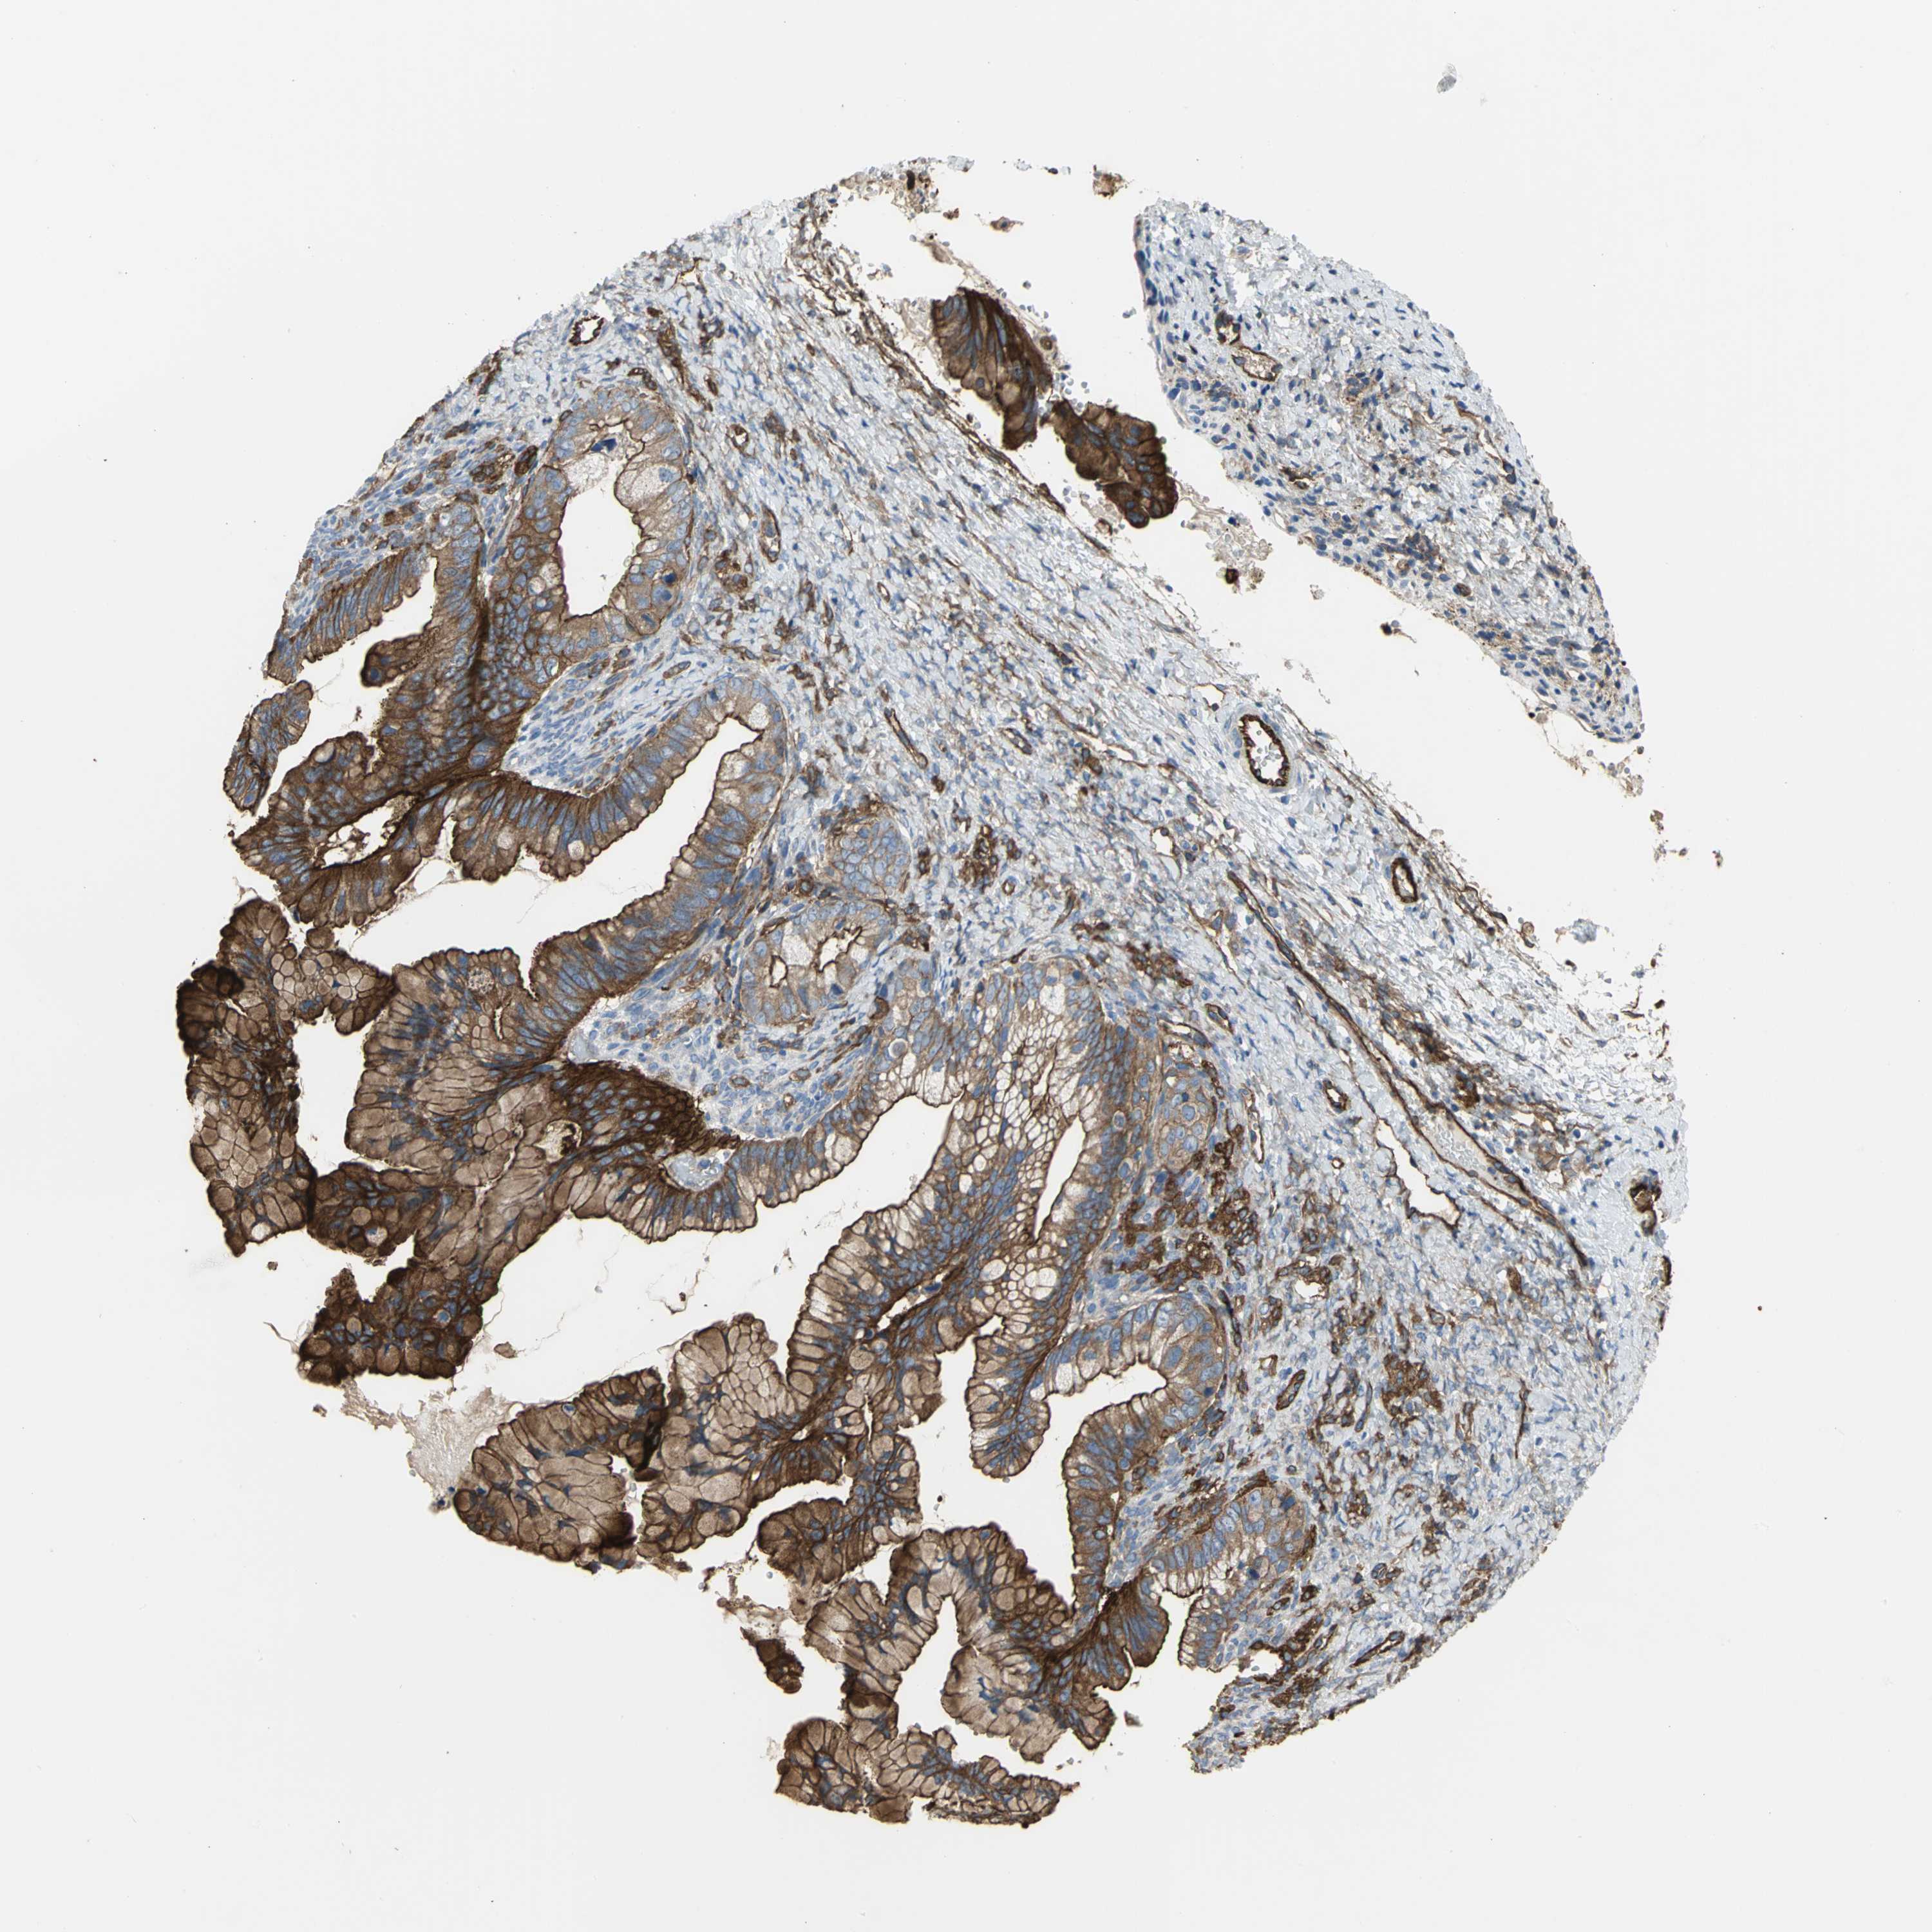

OVARIAN CANCER - Protein expressioni

A mouse-over function shows sample information and annotation data. Click on an image to view it in a full screen mode. Samples can be filtered based on level of antibody staining by selecting one or several of the following categories: high, medium, low and not detected. The assay and annotation is described here.

Note that samples used for immunohistochemistry by the Human Protein Atlas do not correspond to samples in the TCGA dataset.

Antibody stainingi

Antibody staining in the annotated cell types in the current human tissue is reported as not detected, low, medium, or high, based on conventional immunohistochemistry profiling in selected tissues. This score is based on the combination of the staining intensity and fraction of stained cells.

Each image is clickable and will lead to virtual microscopy that enables deeper exploration of all samples and also displays staining intensity scores, fraction scores and subcellular localization as well as patient and tissue information for each sample.

Antibody HPA004747

Antibody HPA004886

Antibody CAB019322

Cystadenocarcinoma, serous, NOS

Carcinoma, endometroid

Carcinoma, NOS

Cystadenocarcinoma, mucinous, NOS